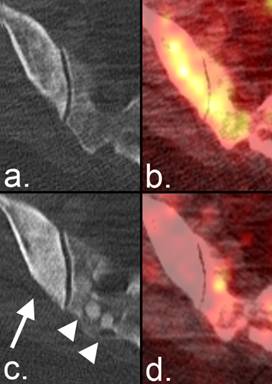

Figure 5

Partial response on radiographs according to the MDA criteria. (a) A lytic metastasis is seen in the C7 vertebral body on CT in a patient with breast cancer. (b) Fused PET/CT image from the same examination demonstrates FDG uptake representing active tumor. (c) Five weeks later, the lesion developed a sclerotic rim that resulted in a reduction in the size of the lytic area. (d) Fused PET/CT image from the same examination as (c) shows resolution of FDG activity, confirming the positive anatomic response.